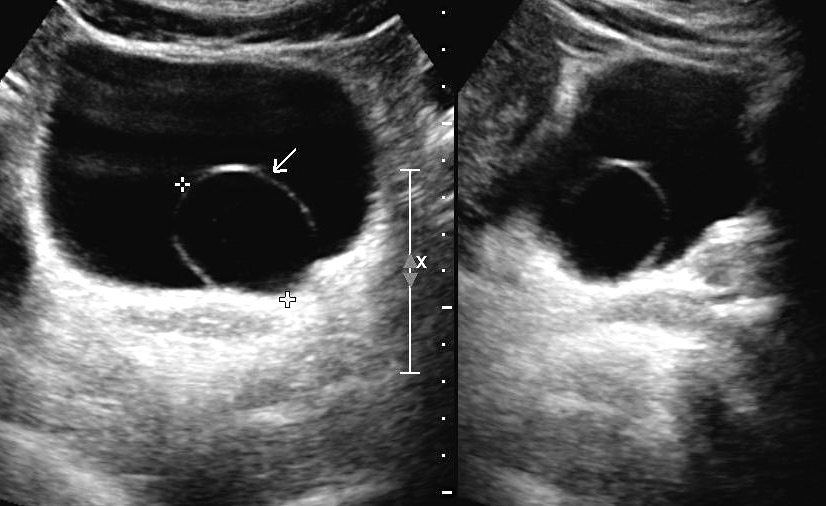

El diagnóstico se realiza por ultrasonido en el que se observa la dilatación quística del tercio distal del ureter, o por urografía excretora o urotomografía en las que se busca el signo de la cabeza de cobra. (se observa la acumulación del medio de contraste en la zona de dilatación.